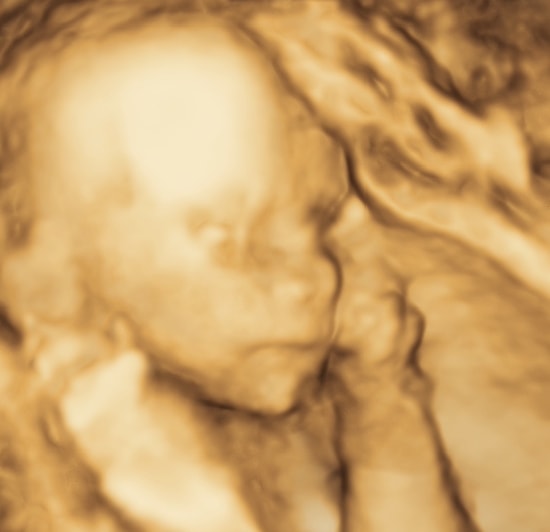

Всё отлично! В малышке 350 грамм и прекрасный носик ❤️

150 грамм ребенка внутри меня гладят себя по голове 💗💗💗